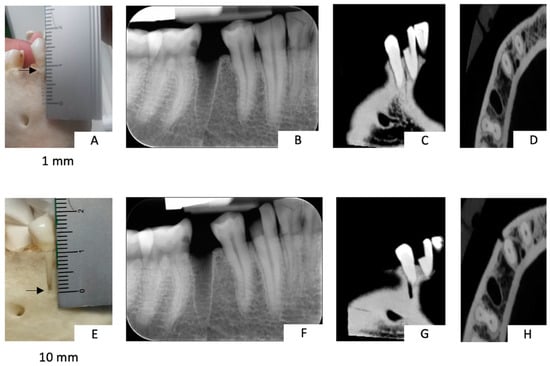

2.5. Case Report: Clinical Analysis

3.3. Case Report: Clinical Analysis